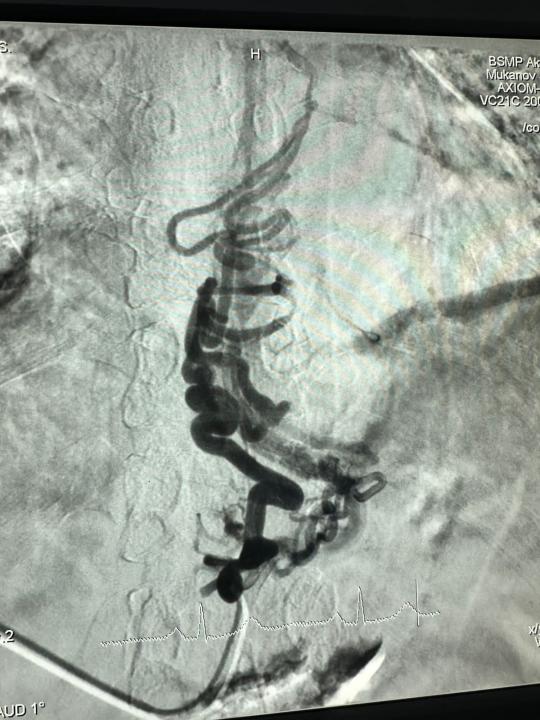

Данная высокотехнологичная операция называется ретроградная трансвенозная облитерация с использованием спиралей (CARTO — Coil-assisted retrograde transvenous obliteration).

Ретроградная трансвенозная облитерация вен с помощью спиралей (CARTO) является современным, безопасным и эффективным вариантом лечения портального гипертензивного варикозного кровотечения, используемый интервенционными радиологами. Процедура включает в себе блокировку расширенных вен при помощи спиралей, специального клея и эмболов, что снижает риск их разрыва. Операция проводится под местной анестезией, с применением ангиографической установки. Подобные дорогостоящие операции проводятся для пациентов бесплатно за счёт средств системы медицинского страхования.